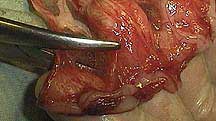

Here is a different case showing the bruising and compromised blood supply that can occur when the intestines are trapped

Intestines are not the only organ that can be bruised during abdominal trauma or a hernia. The kidney on the left has been traumatized as evidenced by the severe bruising when compare to the other kidney.